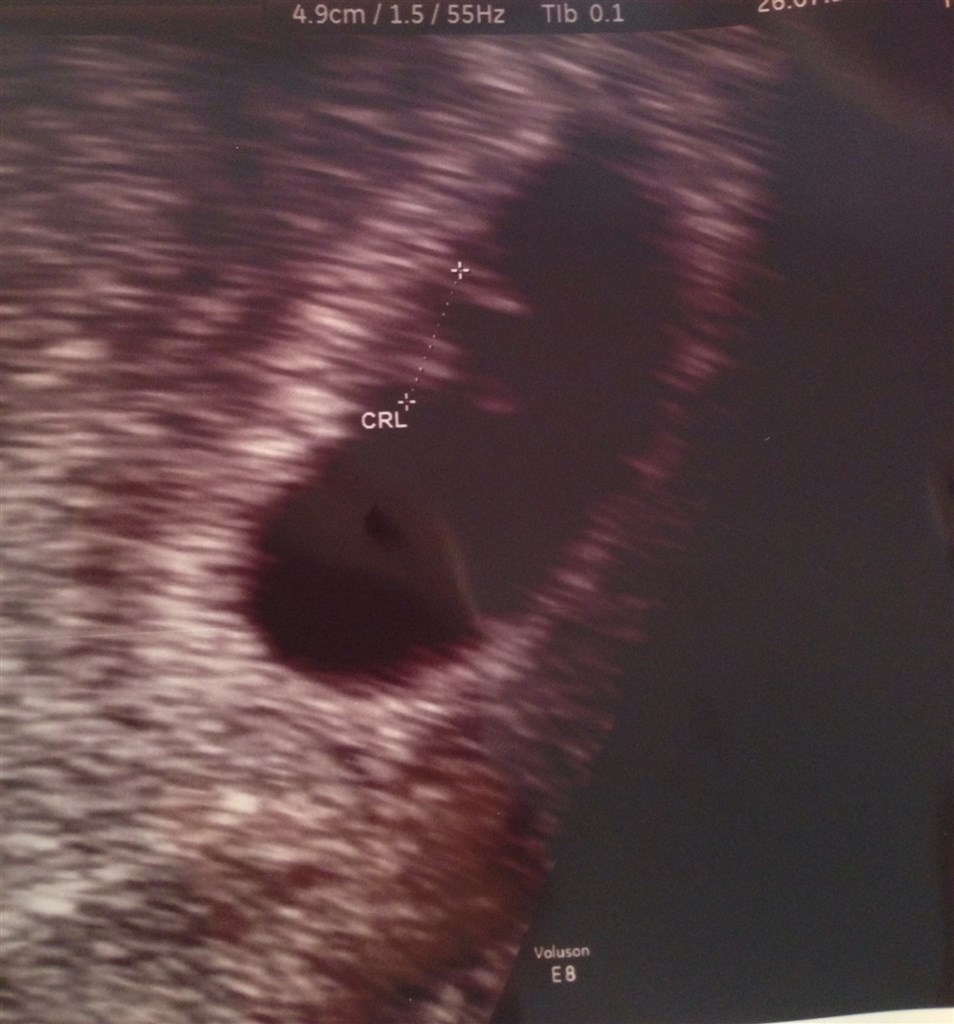

Så har jeg været til scanning. I følge mine egne beregninger er jeg 6+3, men lægen der scannede mig målte den lille til at jeg var ca. 6+1.

Den sad hvor den skulle og vi kunne se og høre et lille fint hjerte blinke.